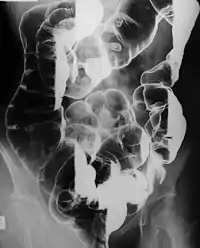

Захворювання проявляється численними доброякісними гамартомними поліпами в шлунково-кишковому тракті. В одного пацієнта може бути більше сотні таких гамартом. Розміри поліпів приблизно 1-5 мм, але вони можуть виростати значно більшими. У 64 % пацієнтів їх виявляють і в тонкому кишечнику, у 64 % — у товстому кишечнику, у 49 % — в шлунку і у 32 % — в прямій кишці. Описані гамартомні поліпи в ниркових лоханках, в сечовому міхурі, в легенях і ніздрях.[6].

Вперше поліпи проявлять себе клінічно, як правило, у віці 10-30 років. У 43 % пацієнтів вони призводять до кишкової непрохідності, у 23 % маніфестують абдомінальним (колікоподібним) болем, у 14 % ректальними крововиділеннями чи кров'янистими випорожненнями. Часто призводить до інвагінації тонкого кишечника (у 5 % товстого). Через часті кровотечі може розвинутися вторинна анемія.